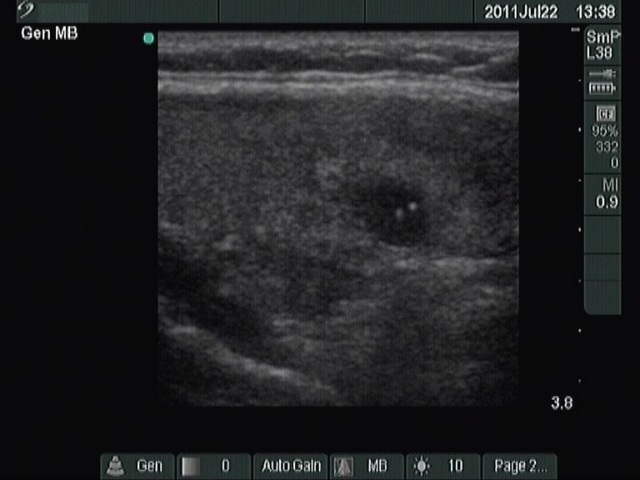

Hashimoto's thyroiditis without any nodule (histological diagnosis) - case 1520 |

The coexistence of tiny punctate granules and similarly bright lines is the hallmark of connective tissue. There is a brighter and relatively large granule in the ventral small lesion in the upper image which might be either a punctate echogenic focus or a sign of fibrotic changes.